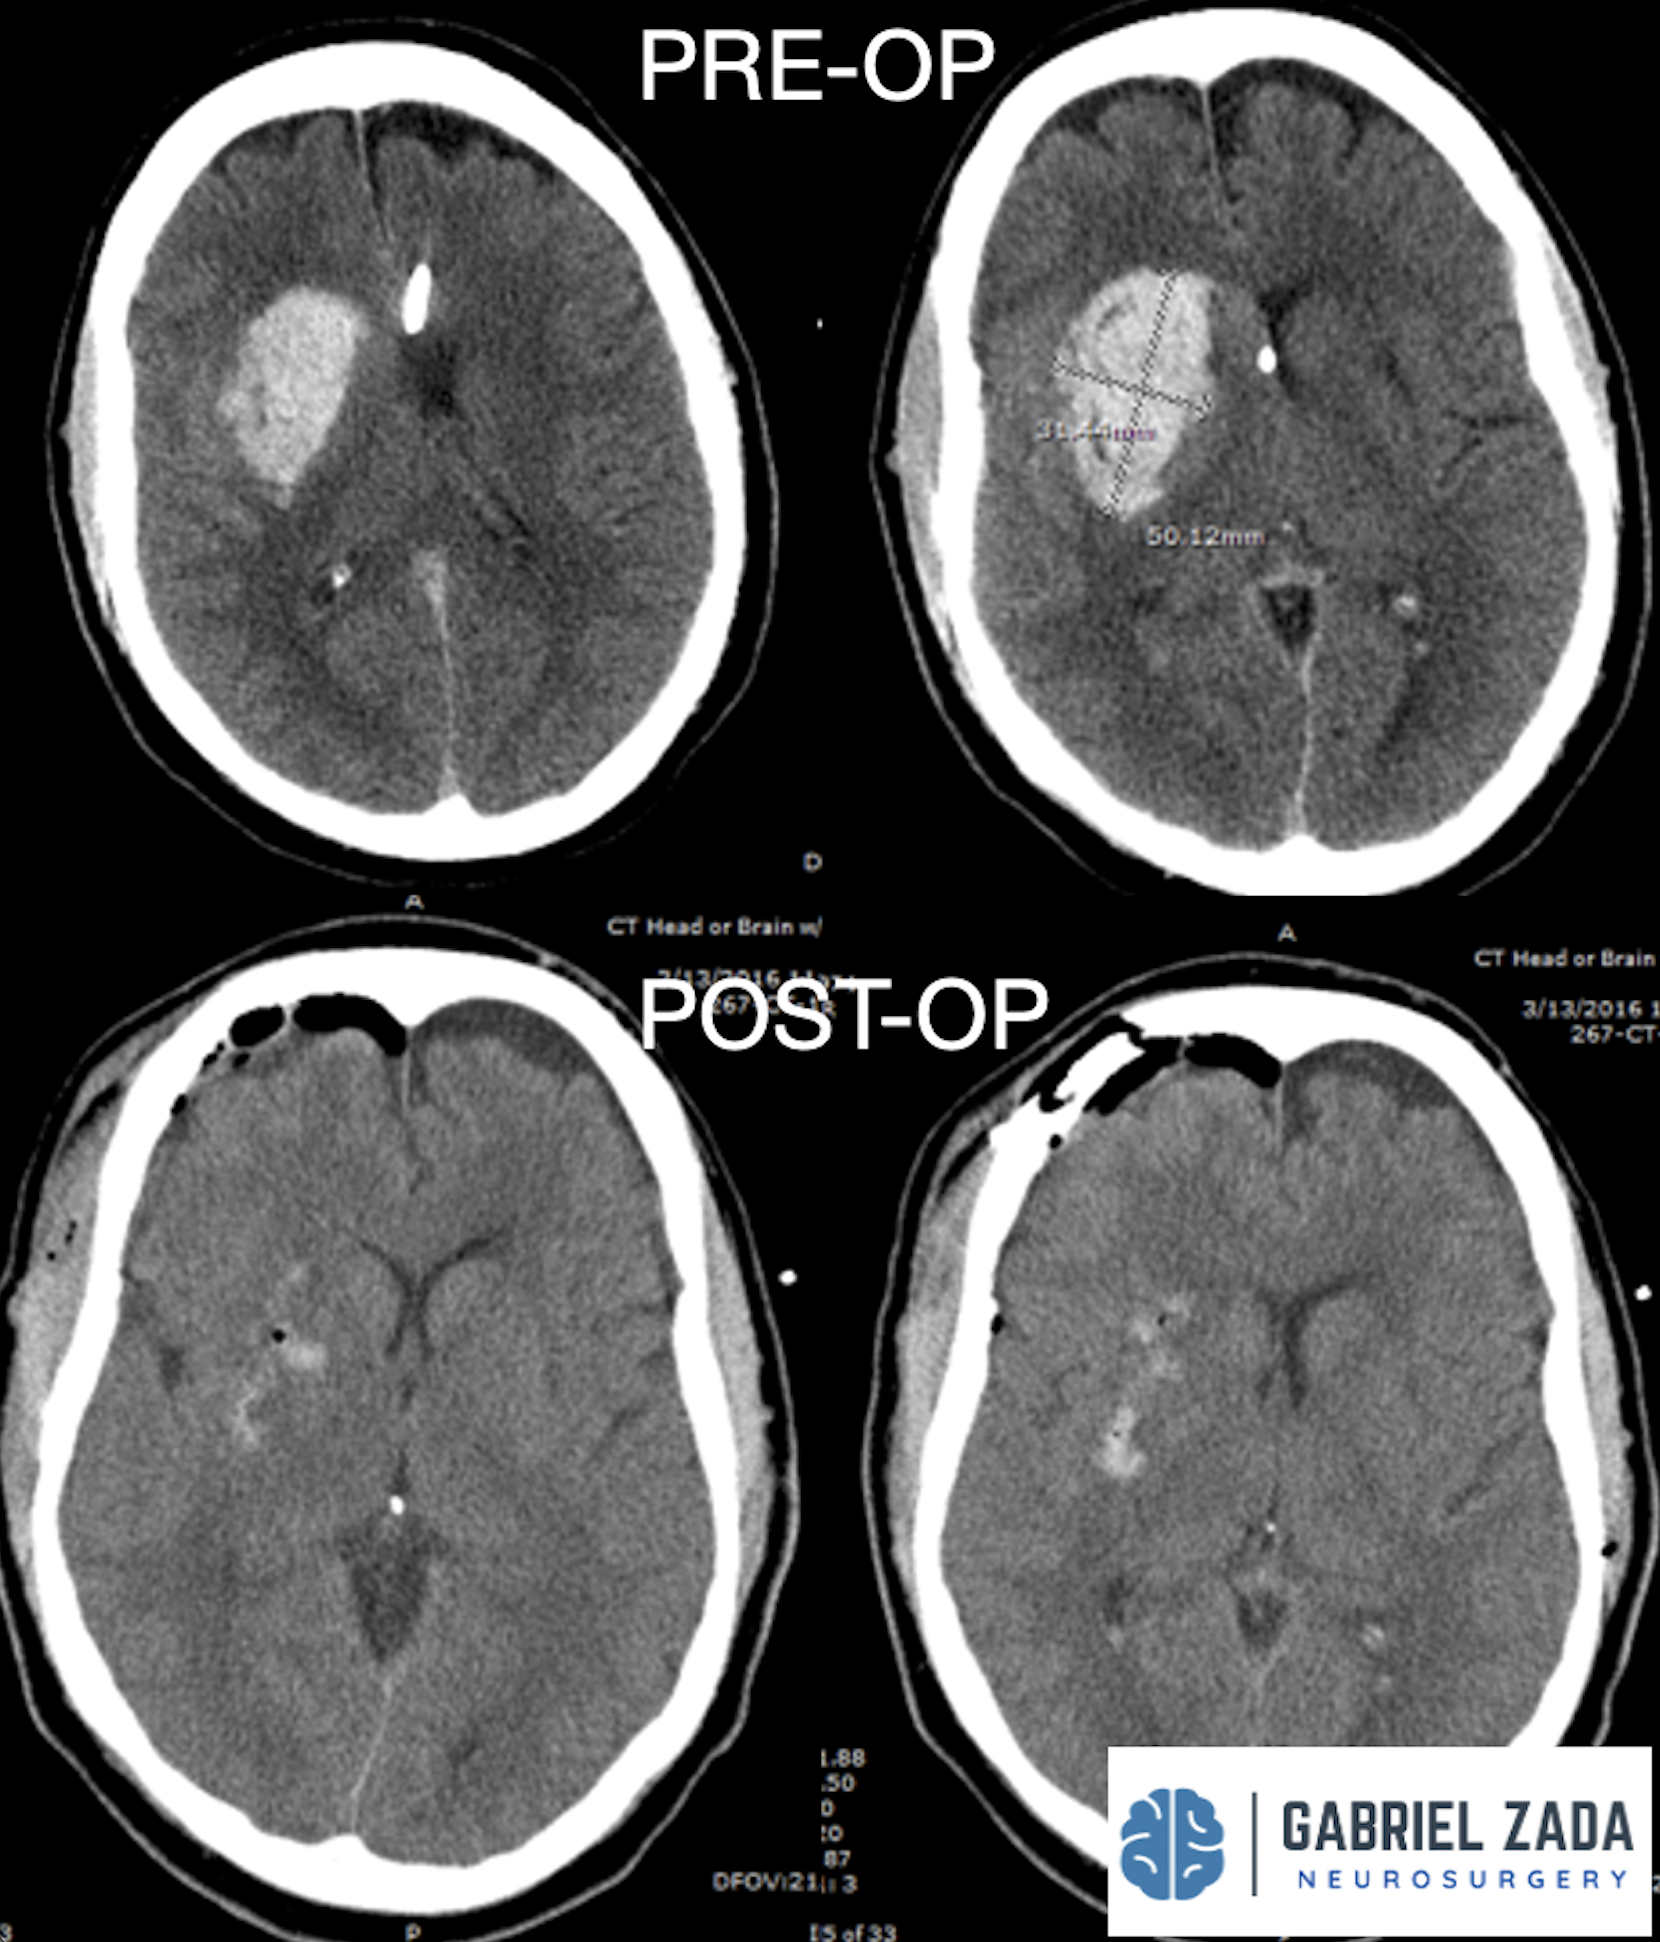

Explore this comprehensive gallery featuring pre‑ and post‑operative imaging of patients with skull‑base tumors treated by Gabriel Zada, MD, MS, FAANS, FACS. These cases highlight Dr. Zada’s expertise in advanced neurosurgical techniques and outcomes.

*Representative cases shown for educational purposes. All images de-identified. Individual results vary.